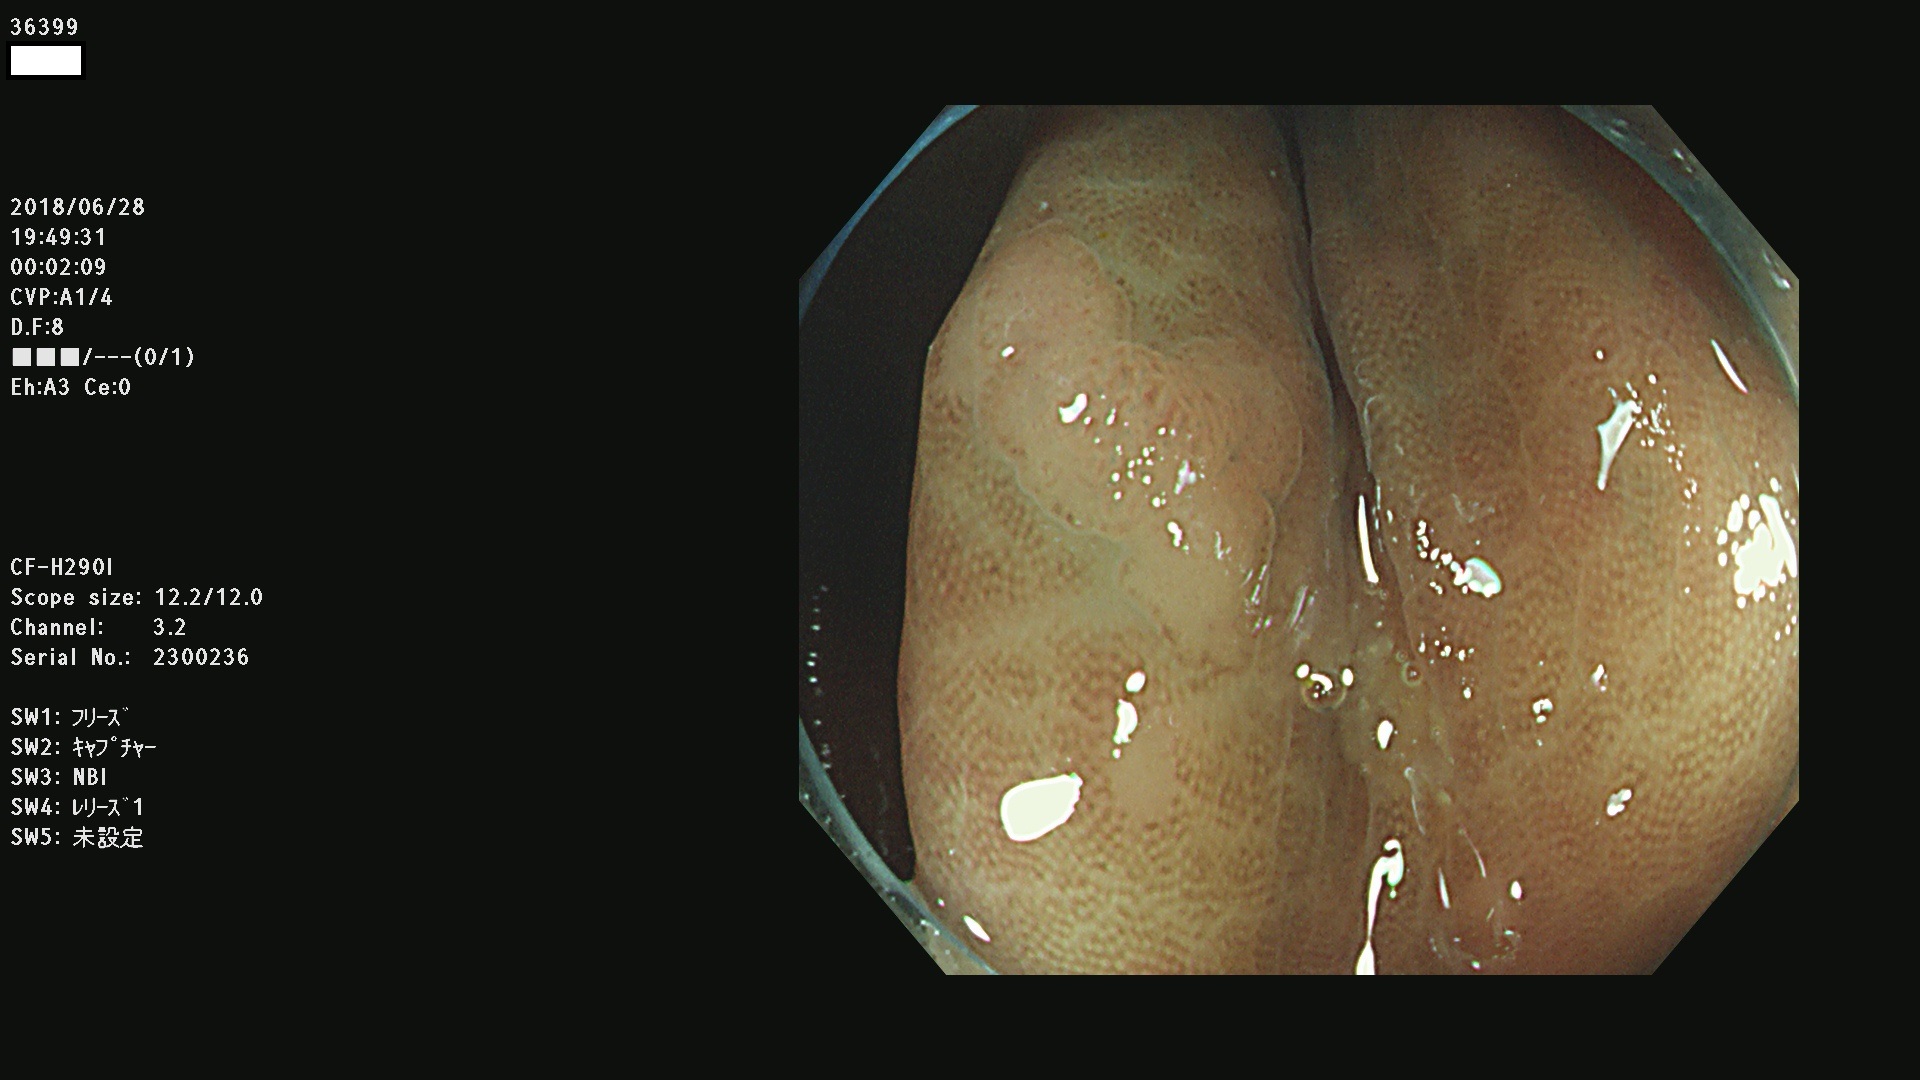

腺腫発見率 68 % (カルテ番号 36300〜36399の100名の方の検査結果で集計)大腸癌検診最新情報

以下のカルテ番号の方に腺腫(Adenoma,Group3〜5)が見つかりました(集計法)

36300 36302 36305 36306 36307 36308 36310 36311 36312 36313 36314 36315 36316 36318 36321 36322 36324 36325 36326 36327 36330 36332 36333 36334 36335(SSAPのみ) 36337 36338 36339(SSAPのみ) 36340 36341 36342(SSAPのみ) 36343 36344 36346 36348 36349 36351 36353 36354 36355(SSAPのみ) 36356 36357 36358 36359 36364 36365 36366 36367 36370 36374 36376 36379 36381 36382 36383 36384 36385 36387 36388 36389 36390 36392 36393 36395 36396 36398 36399

発見困難で危険性の高い平坦型病変(上記100名より抽出) ![]()